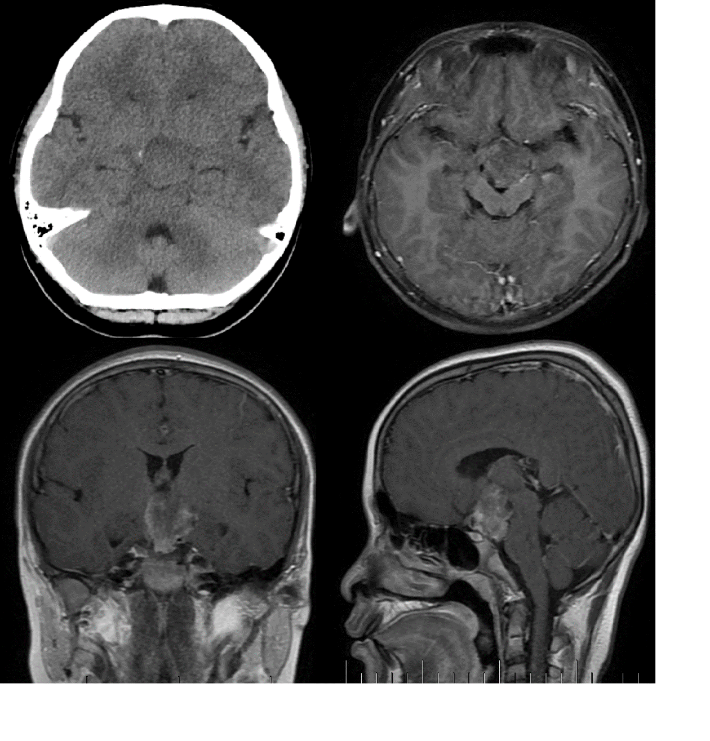

辅助检查:术前CT提示患儿鞍上等密度占位性病变,未见钙化。MRI显示鞍上大小约3.2*3.1*3.6cm异常信号占位性病变,与下丘脑等结构边界不清,注药后轻度不均匀强化(图1)。

图1.术前头部CT及MRI T1增强矢冠轴位